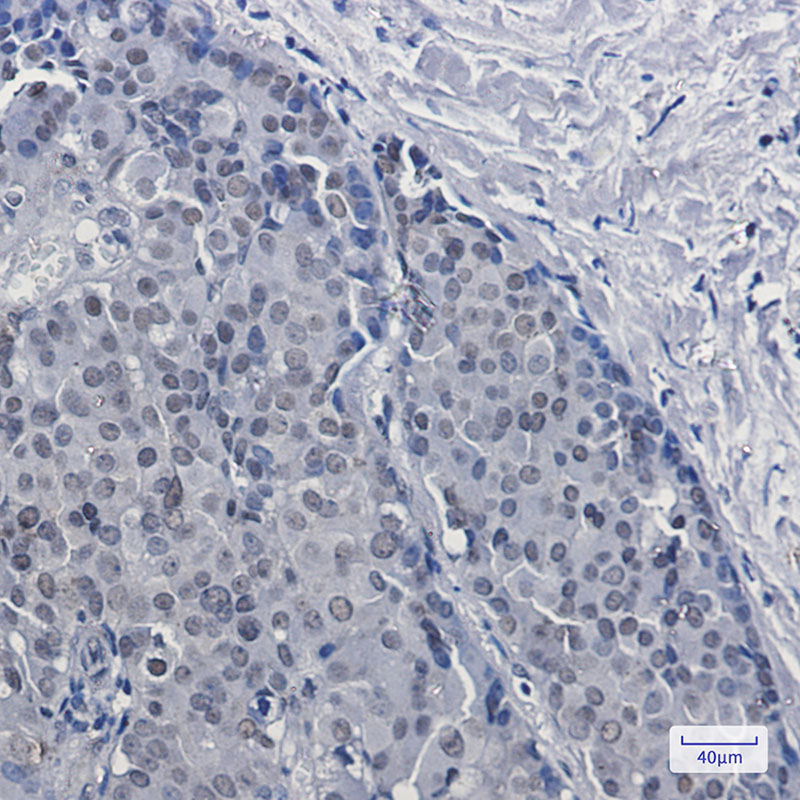

- Immunohistochemistry analysis of paraffin-embedded Human breast cancer tissue using DKC1 antibody. High-pressure and temperature Sodium Citrate pH 6.0 was used for antigen retrieval.